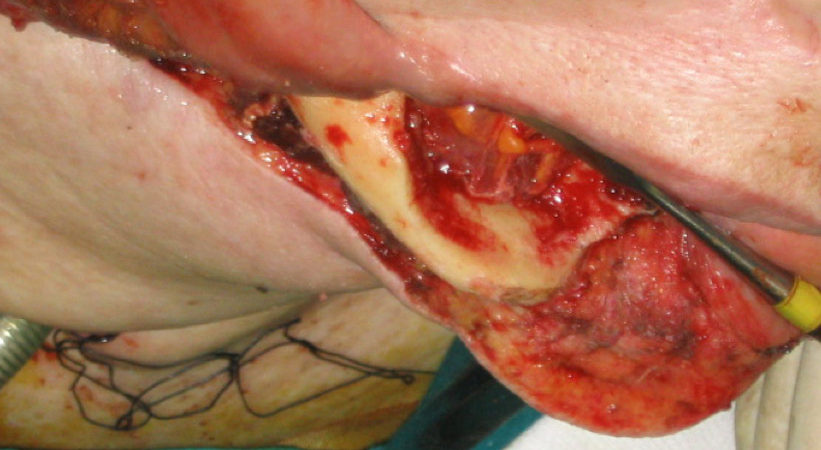

CASO CLINICO N° 1

Donna di 76 anni portatrice di un carcinoma squamoso del trigono retromolare infiltrante l’osso mandibolare T4N0.

La paziente è stata sottoposta ad intervento “commando”.